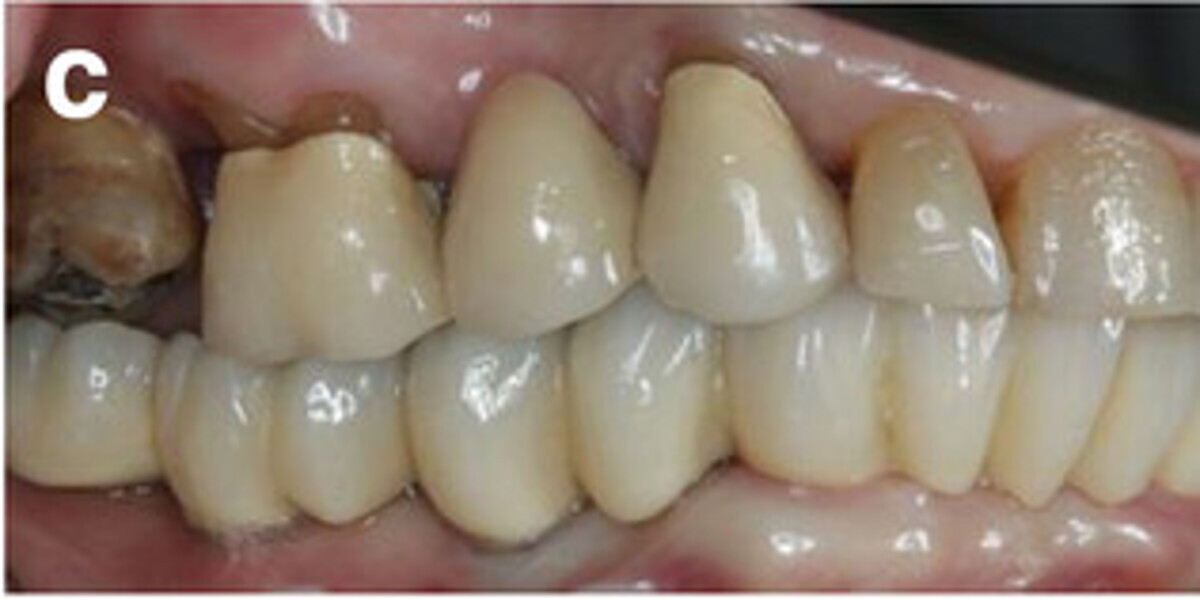

Fig. 14a: Occlusal, frontal and lateral views on the day of delivery, showing healthy peri-implant mucosal conditions (a) and the final CAD/CAM restoration in situ (b–e).

Fig. 14b: Occlusal, frontal and lateral views on the day of delivery, showing healthy peri-implant mucosal conditions (a) and the final CAD/CAM restoration in situ (b–e).

Fig. 14c: Occlusal, frontal and lateral views on the day of delivery, showing healthy peri-implant mucosal conditions (a) and the final CAD/CAM restoration in situ (b–e).

Fig. 14d: Occlusal, frontal and lateral views on the day of delivery, showing healthy peri-implant mucosal conditions (a) and the final CAD/CAM restoration in situ (b–e).

Fig. 14e: Occlusal, frontal and lateral views on the day of delivery, showing healthy peri-implant mucosal conditions (a) and the final CAD/CAM restoration in situ (b–e).